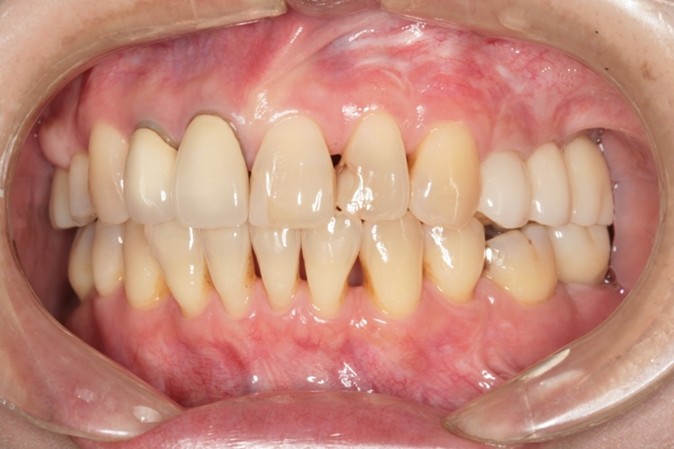

| 年代 | 61歳 |

|---|---|

| 性別 | 男性 |

| 治療内容 | 上顎部分床義歯、下顎全部床義歯で咀嚼障害。高度の骨吸収(インプラント困難な症例) 上額のオールオン6インプラント治療。下顎インプラントオーバーデンチャーによる治療。 レントゲン診断、CT診断、補綴シミュレーション、血液検査、心電図、CT撮影ステント製作、サージカルガイド製作、治療用義歯、静脈内鎮静法抜歯、骨造成手術、サイナスリフト(上顎洞底挙上術)インプラント埋入、骨の治癒期間(4ヶ月)、静脈内鎮静法、2次手術、印象・咬合採得、インプラント上部構造装着、義歯装着、メインテナンス |

| 治療期間 | |

| リスク | 術中の不可抗力によるトラブル(出血など)、術後注意事項を守らないことによる疼痛、感染、上部構造装着後口腔内清掃を怠ったことによるインプラント周囲組織の炎症 |

| 副作用 | 治療後の口腔内清掃、及びメインテナンスを怠ったことによるインプラント周囲粘膜炎またはインプラント周囲炎 |

| 費用 | 4,400,000円(税込) (CT撮影診断、血液検査、心電図モニター、補綴シュミュレーション、治療用義歯、サージカルガイド製作、静脈内鎮静法、インプラント埋入、骨造成手術、サイナスリフト(上顎洞底挙上術)投薬、2次手術、印象・咬合採得、インプラント上部構造などを含む) |